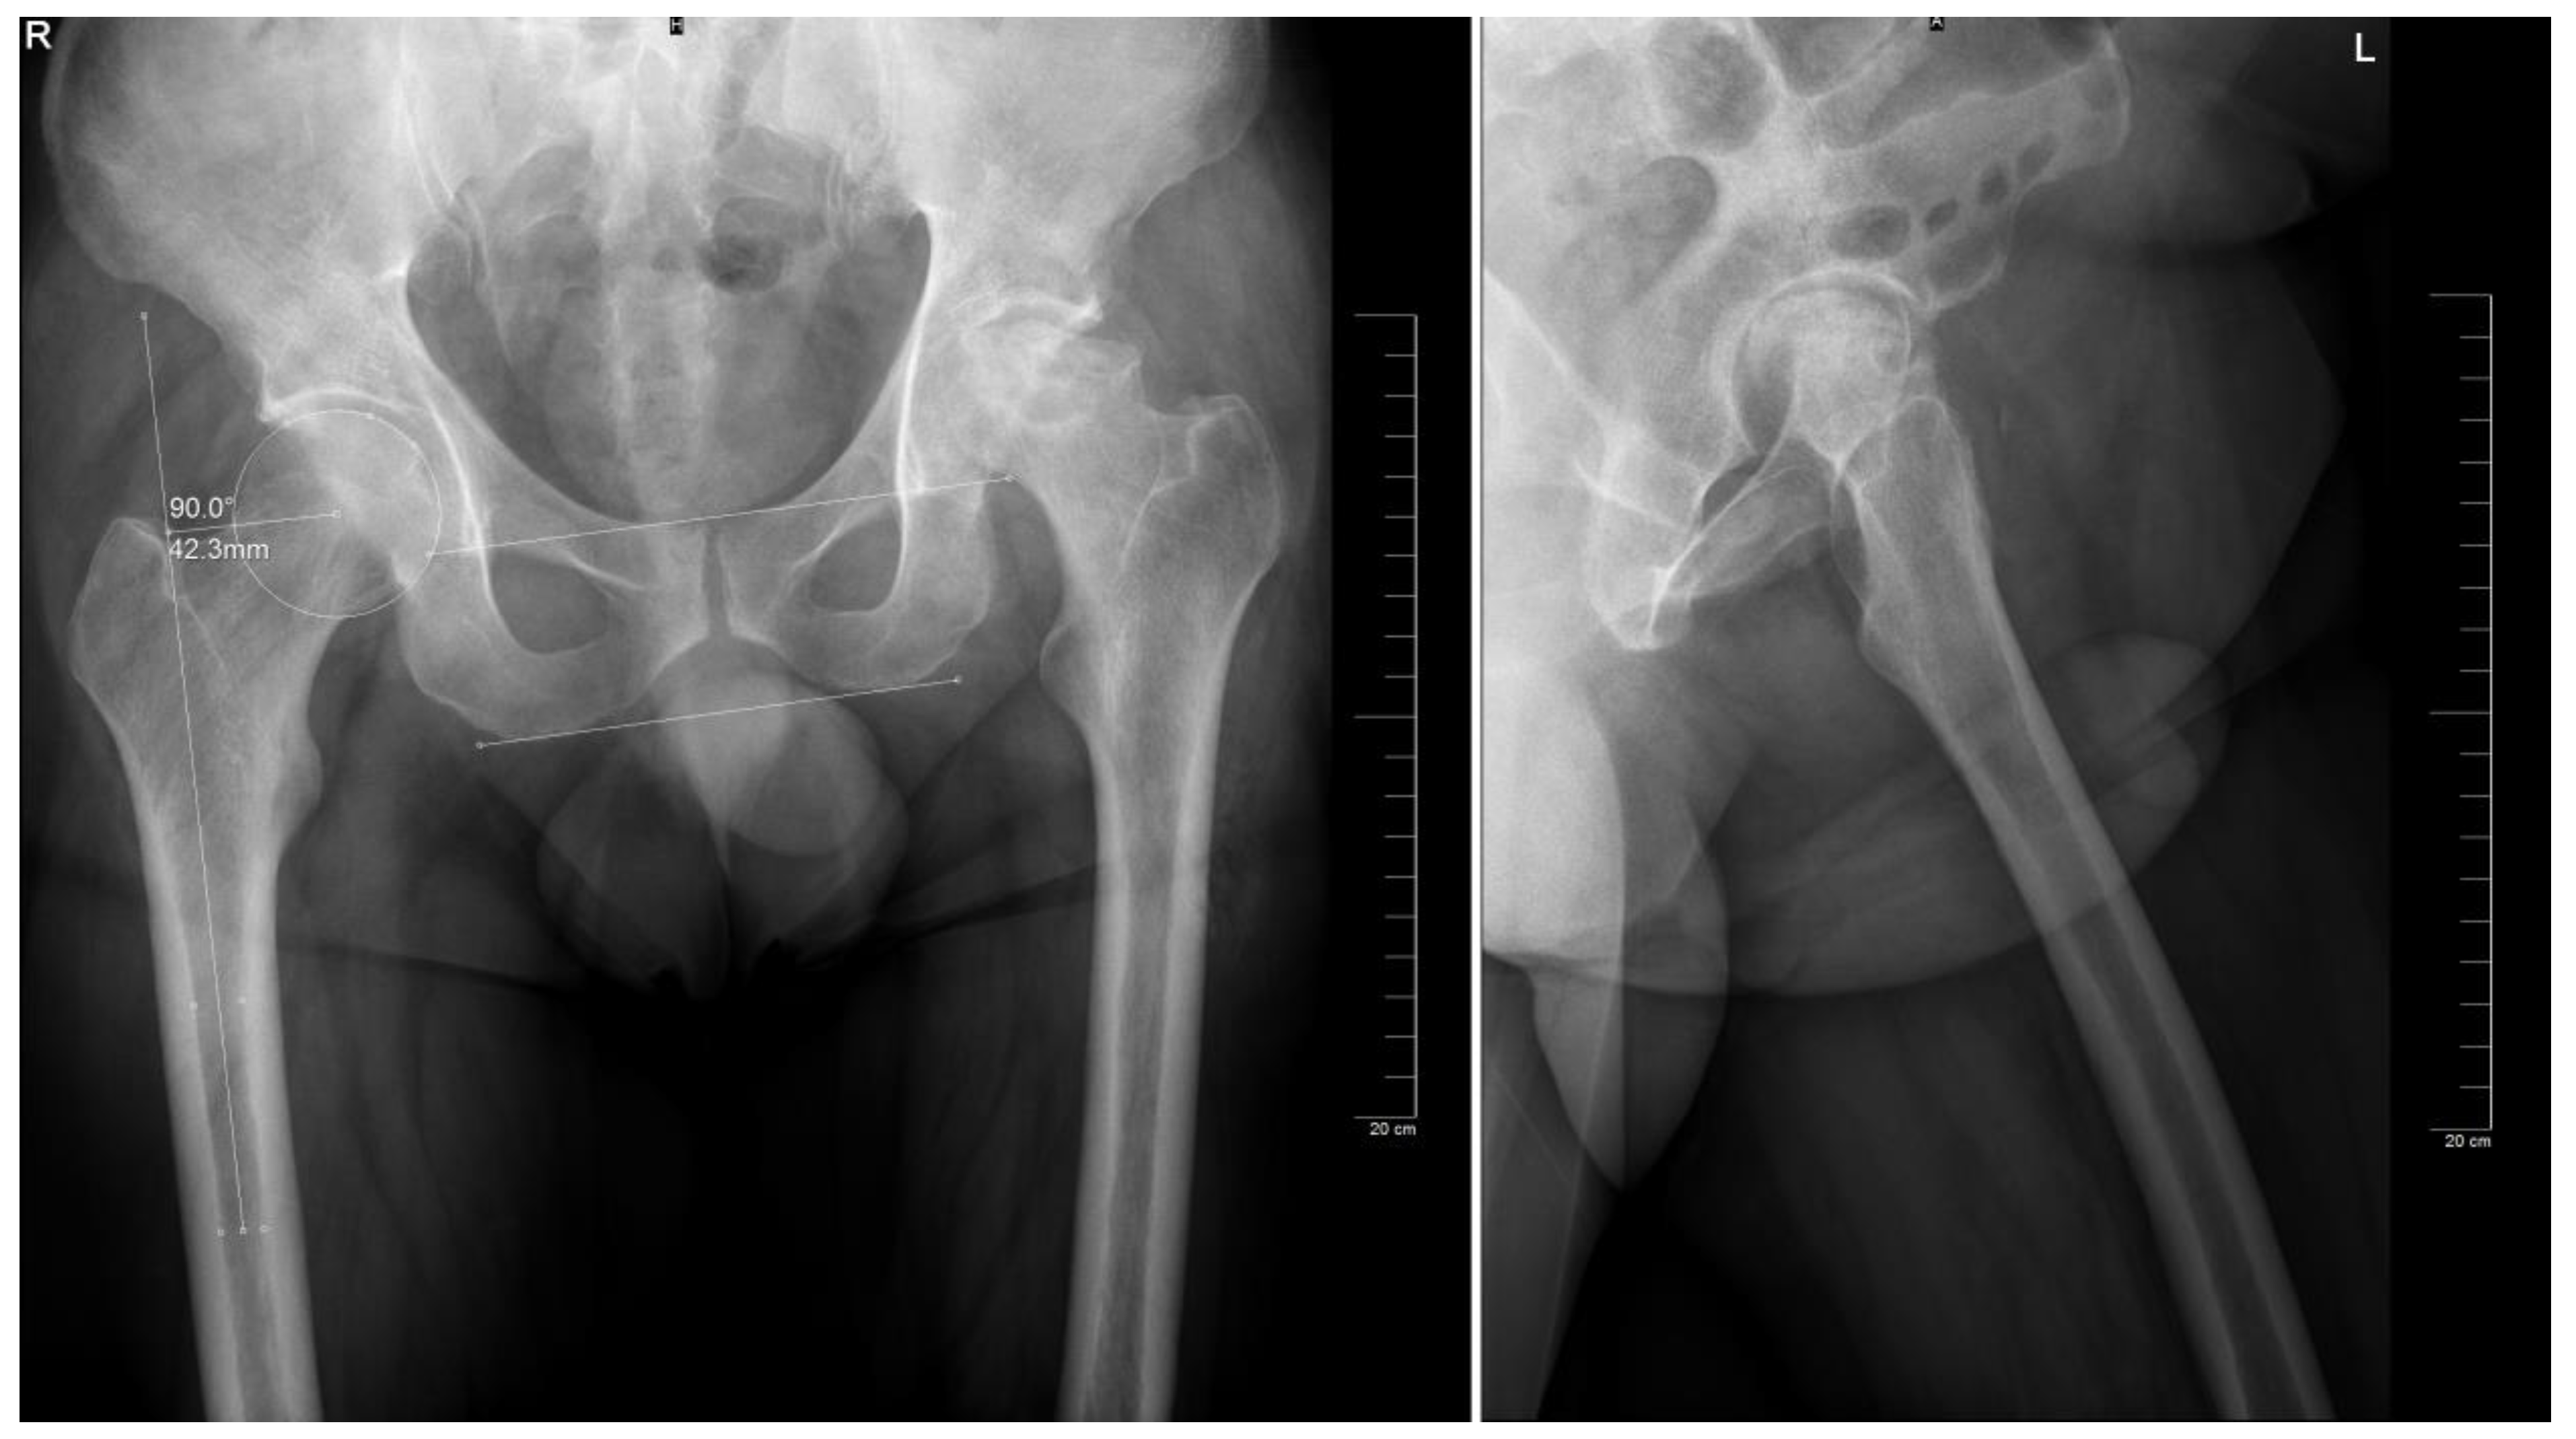

The preoperative planning was performed manually in several phases. Starting with the anteroposterior view, the X-ray magnification is determined. Next, the landmarks are identified: the center of the femoral head, teardrop, anatomical axis of the non-target femur, and the ilioischial and transacetabular teardrop lines (Figure 1). The acetabular component size that fits the contour of the acetabulum was selected. The medial border is defined as the teardrop, and the cup is placed at 45 degrees of abduction. Afterward, the femoral component size that fits most precisely the contour of the canal is chosen, keeping in mind that it should be in contact with the lateral and medial cortex and must be in line with the anatomical axis of the femur. The upper part of the stem component must be located in the piriform fossa. The leg length discrepancy (LLD) is determined by the perpendicular distance from the middle of the lesser trochanter to the horizontal line drawn through the base of both teardrops, and the femoral medial offset (FMO) is calculated as the distance from the center of the femoral head perpendicular to the anatomical axis of the femur. The planning is performed on the lateral view using a similar approach (Figure 2). The acetabular template cup of appropriate size is placed with approximately 45 degrees of abduction. The medial border of the acetabular cup is positioned next to the ilioischial line and in close contact with the teardrop. The anatomical axis of the femur is marked, and the suitable femoral stem is chosen and positioned to fill the medullary canal. Postoperative radiographs are routinely performed to confirm proper positioning (Figure 3).

Figure 3. Postoperative aspect of the implant on the anteroposterior and lateral view, respectively. Note: actual implant sizes were size 8 for the femoral component and size 56 for the acetabular component.